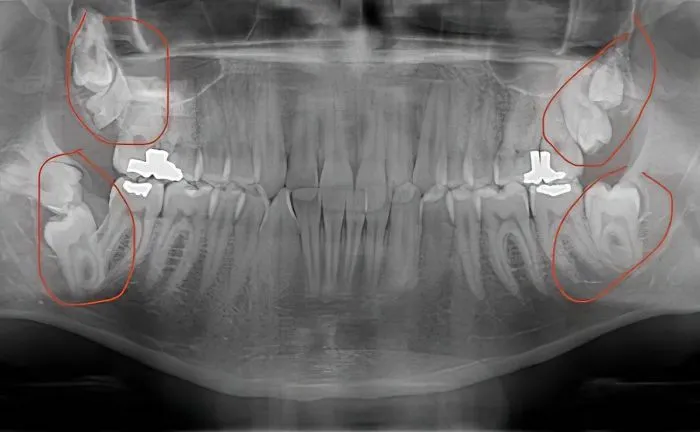

4. У человека было семь зубов мудрости. Ему их удалили. У большинства людей четыре зуба мудрости, по одному в каждом углу

— Если вам интересно, процедуру мне делали под наркозом. Но на извлечение зубов ушло 4 часа.